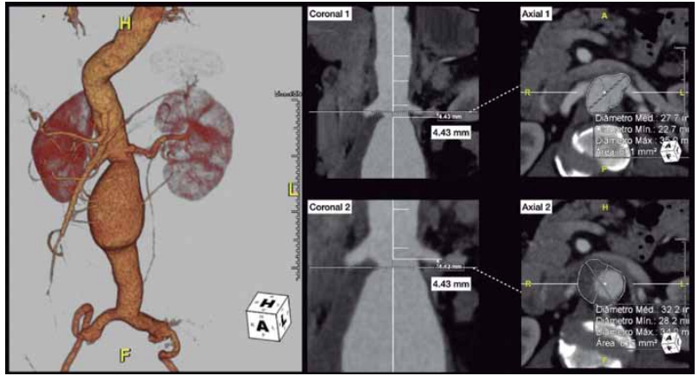

Uma paciente de 65 anos, tabagista ativa, interna pelo pronto atendimento com um quadro de dor lombar de forte intensidade, associado a mal-estar e sudorese fria. Seu exame físico na admissão revela pulsos amplos, com frequência cardíaca de 70 bpm e pressão arterial de 130 x 90 mmHg. Em virtude do quadro, uma angiotomografia complementar é realizada, sendo identificada rotura de aneurisma de aorta.

Alguns cortes tomográficos de interesse são apresentados na figura a seguir:

* As figuras Coronal 1 e Coronal 2 correspondem, respectivamente, ao mesmo plano indicado em Axial 1 e Axial 2 *

Em relação à abordagem cirúrgica, assinale a alternativa correta.